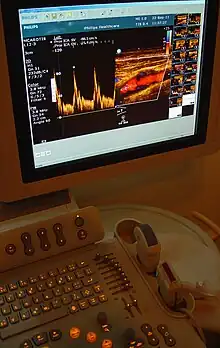

In the 1970s, Strandness and the bio-engineering group at the University of Washington, turned their attention to the use of real-time B-mode scanning. This type of ultrasound would enable physicians to see the vascular structures in real-time. Further research allowed B-mode imaging to be combined with Doppler ultrasound, providing real-time views of the vascular structures and simultaneous hemodynamic information. Today, this type of duplex scanning is used in a variety of ultrasound specialties.[6]

Prior to Strandness' work, the only vascular imaging available to physicians would have been arteriograms, x-rays read from radiopaque dyes injected directly into the bloodstream. Initially, the idea of using ultrasound imaging was met with resistance. Eventually, however, younger physicians were more receptive and accepting of the technology Strandness and his team developed. Although arteriograms are sometimes still used, most physicians today rely upon the non-invasive procedures and real-time information provided by duplex ultrasound scans.[9]

Today, based on the technologies and practices Dr. Strandness developed, vascular ultrasound is a well established field. Technologists, known as vascular sonographers, specialize in this specific branch of ultrasound scanning.[10]